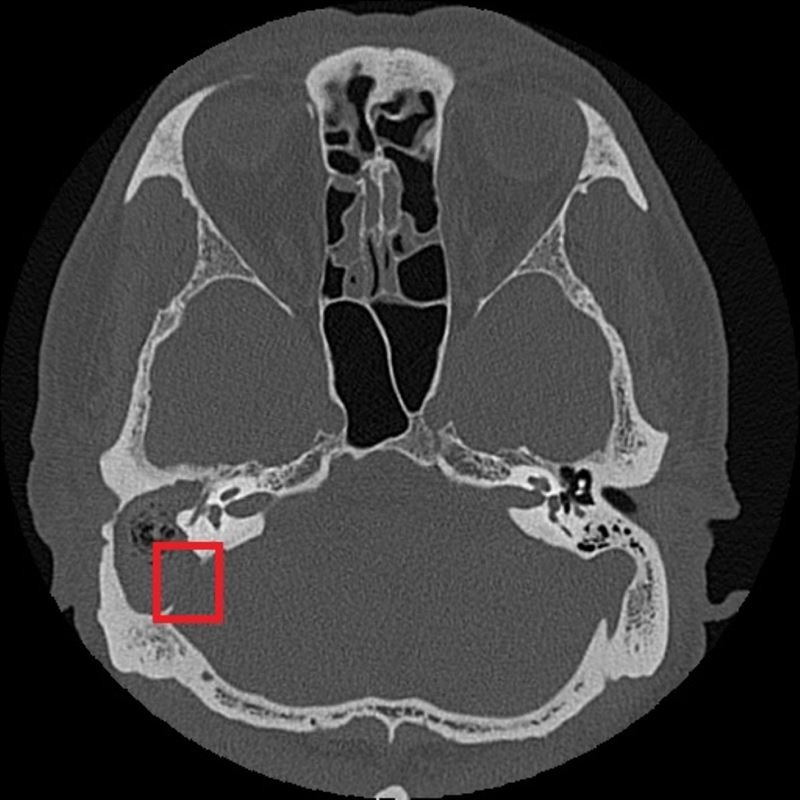

根據《三立新聞網》、《ETtoday新聞雲》報導,台北慈濟醫院耳鼻喉科主治醫師鄭靜雯說明,張先生有慢性中耳炎病史,檢查時發現耳道內都是膿液和皮屑,清理用藥後不僅沒緩解,右臉還「顏面神經麻痺」癱瘓。經過顳骨電腦斷層,張先生確診為「慢性中耳炎併發膽脂瘤」。雖然膽脂瘤是良性的,但已經侵蝕到顱底骨質,導致神經壓迫、右臉面癱。

示意圖非當事人,翻攝自台北慈濟醫院

鄭靜雯醫師說明,扁平上皮細胞長期累積角質,在耳朵裡堆積成膽脂瘤,在中耳或乳突部位較常見。後天的膽脂瘤多和慢性中耳炎相關,耳朵長期發炎、鼓膜穿孔,逐漸在中耳腔形成膽脂瘤,持續侵蝕骨質、破壞聽小骨。張先生住院後先是控制發炎感染,穩定發炎後才手術清除病灶、修補重建鼓室組織,所幸術後恢復良好。